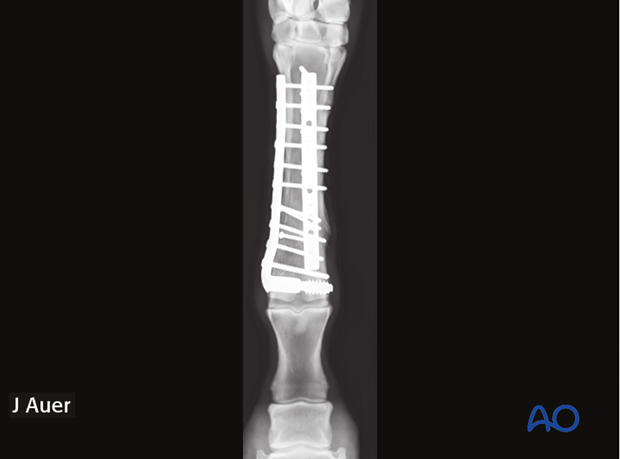

The fracture is anatomically reduced and repaired with one or two plates spanning the entire bone and applied at 90° relative to each other (left). In small ponies, some foals and selective cases of adult horses only one plate may be selected (right).